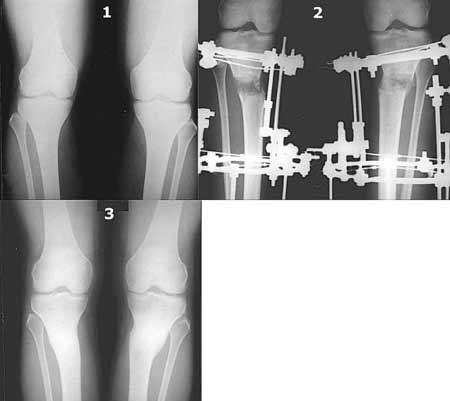

Картинки - в приложении.Будут вопросы - готов ответить.

Ещё картинка - схема. Хотя у Соломина всё написано.

Вот ещё картинки, которые отправлял в Ортопод. Коррекция кривизны и удлинение на 3 см.

Мне представляется оптимальным на уровне 3-4 линии (т.е. как раз посредине отмеченной зоны). Если рассчимтываешь делать медиализацию, то параллельно суставной поверхности, иначе просто не сдвинешь без джистракции - отломки зацепятся. Если без медиализации - то вообще не имеет значения.

Ты же понимаешь, опыт эмпирический. Было дело - промахивался с метками - делал сантиметра на 2-3 ниже сустава - всё было хорошо.

Сложно только цеплять короткий фрагмент, особенно когда удлинение. Спускался ниже - 5-7 см ниже сустава - тоже всё хорошо. Ниже уже бессмысленно - диафиз, ломать труднее, срастается дольше.